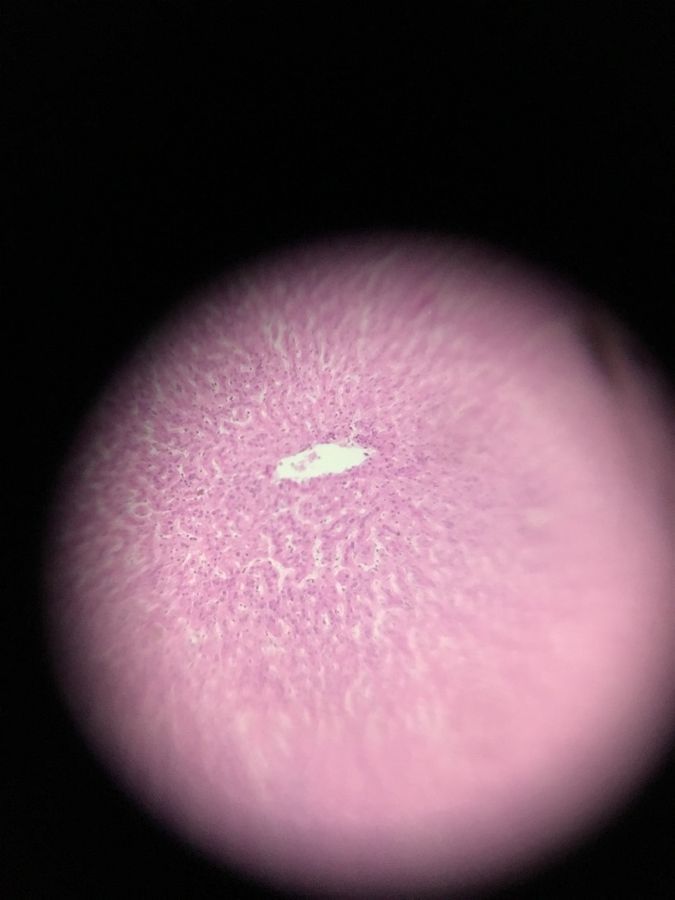

Liver

Used Histology glass slides from the Cell Structure and Function Lab. It was sort of challenging to navigate with the foldscope because the location of the samples varied on the slide. Ended up just really pressing the slide on to the foldscope and using my toe to take a picture on my phone. A decent first try.